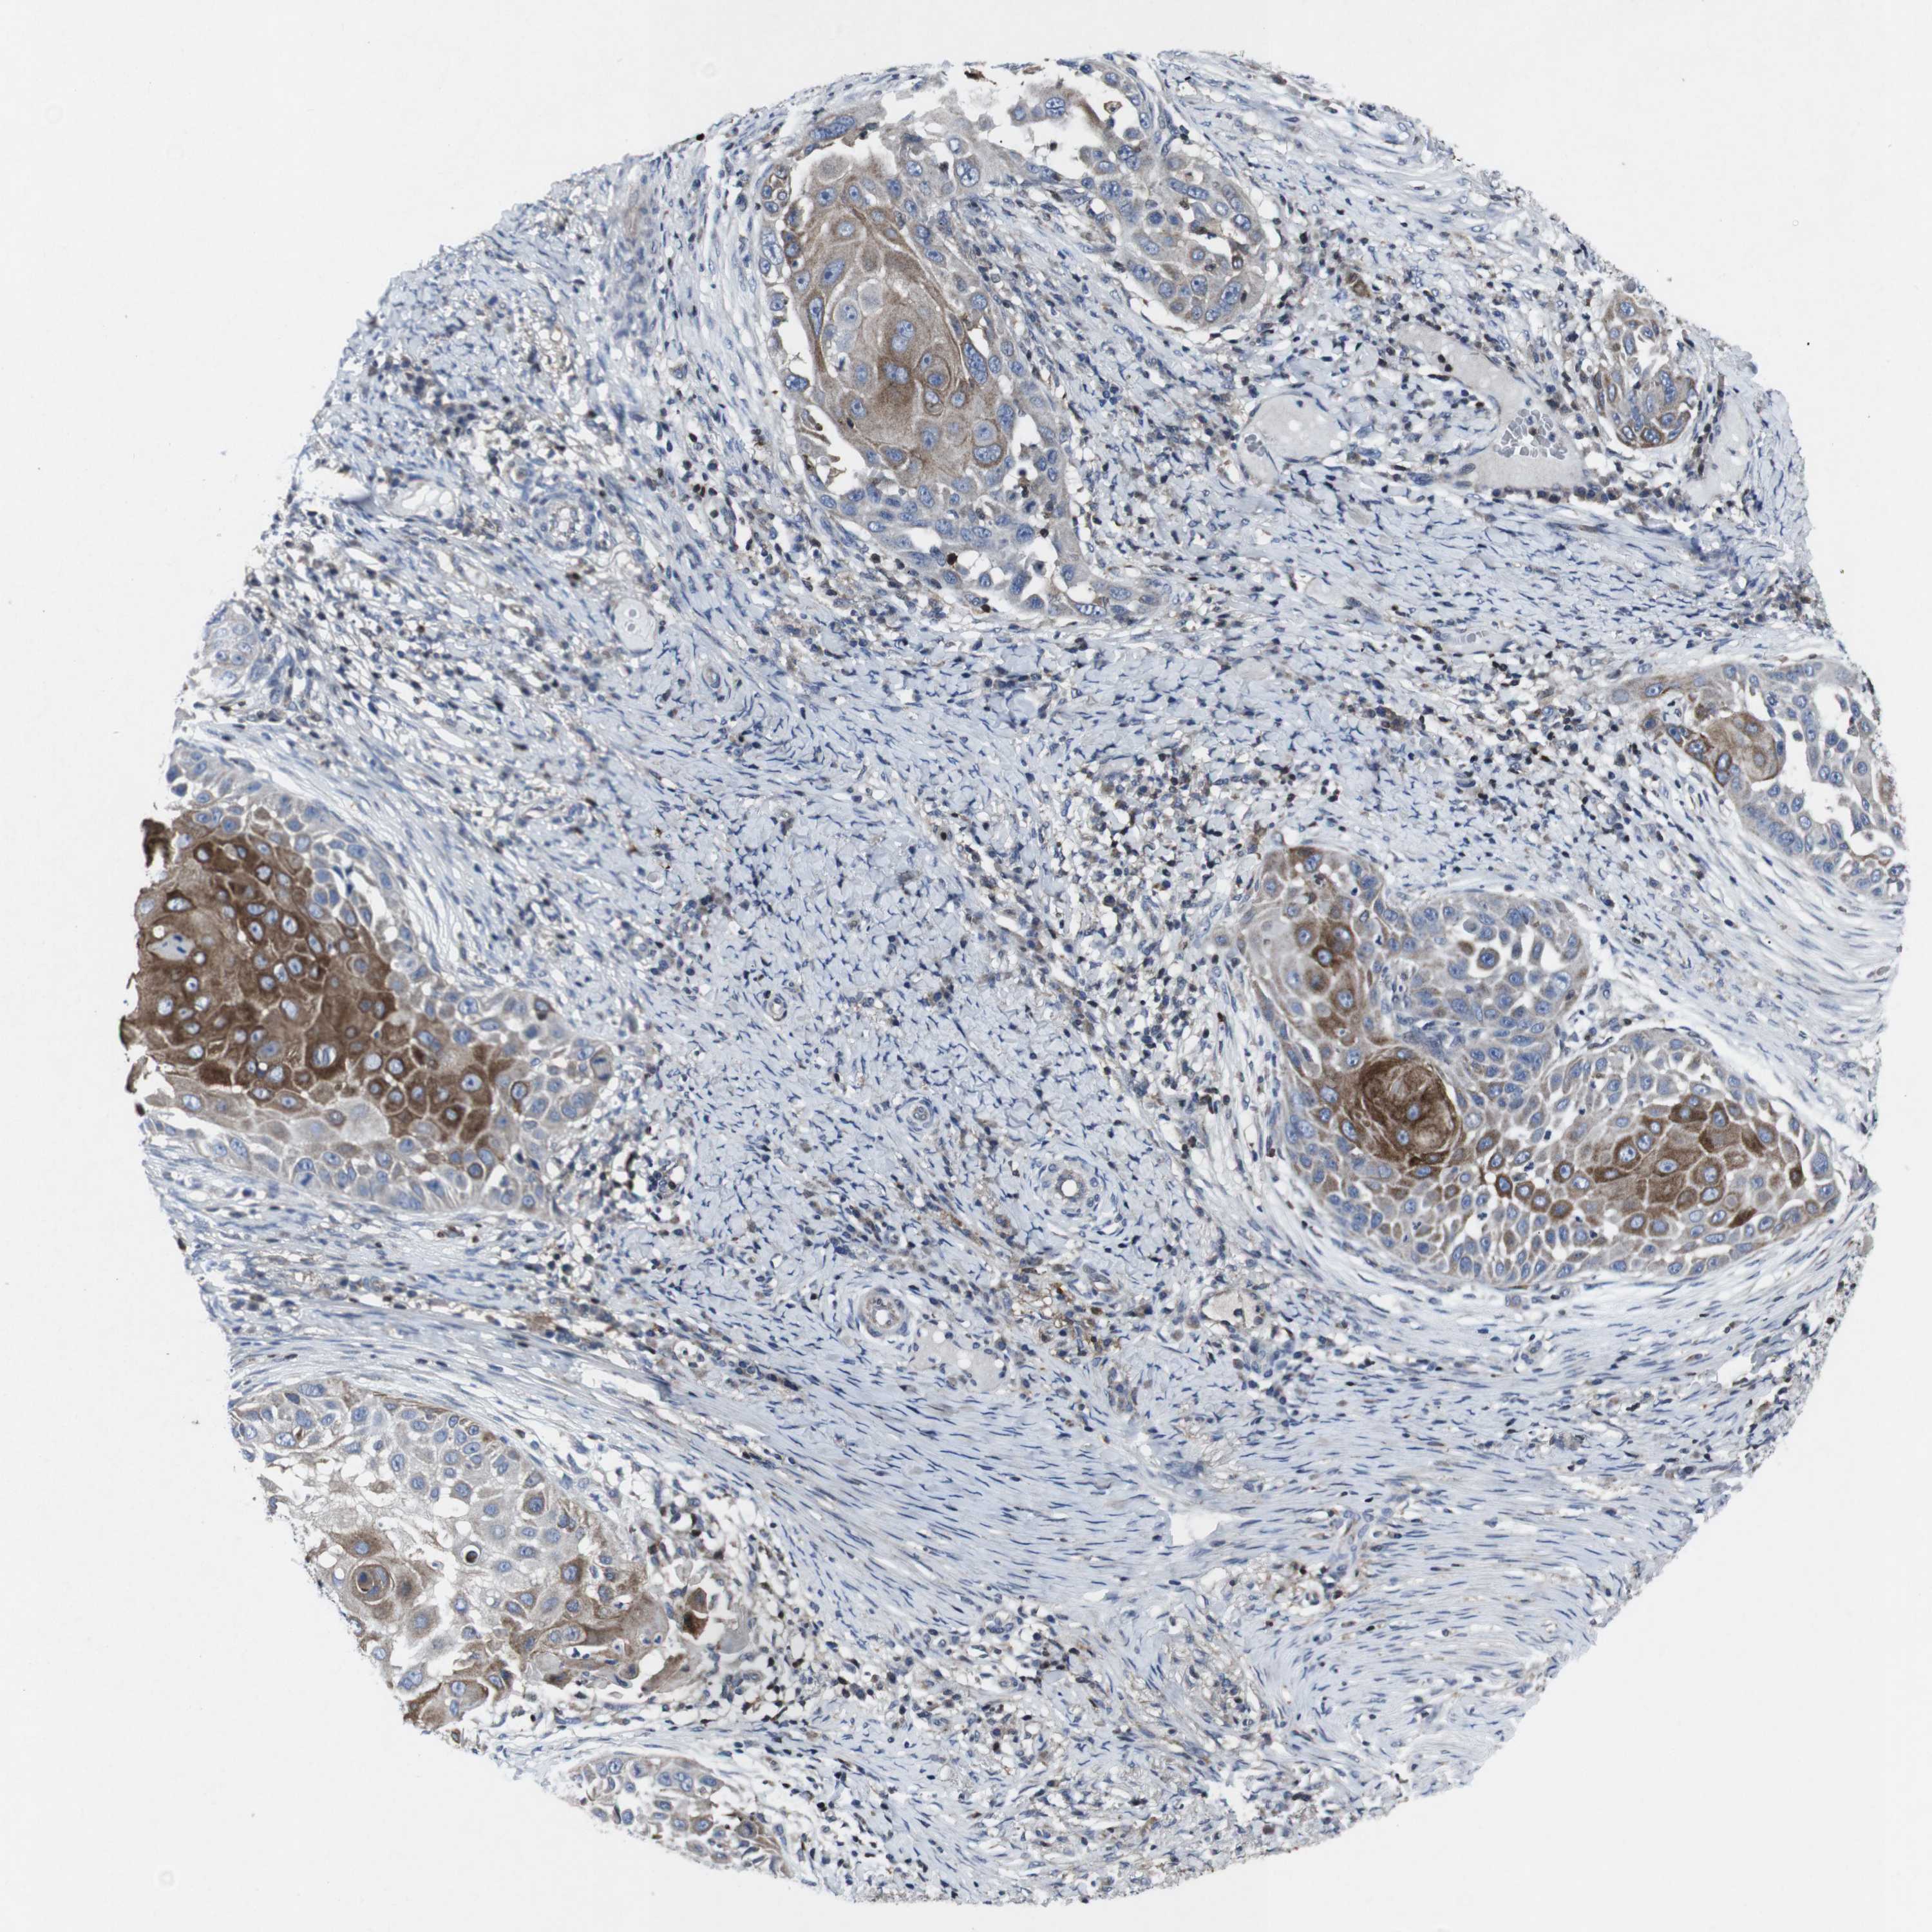

Basal cell and squamous cell cancer

SKIN CANCER - Protein expressioni

A mouse-over function shows sample information and annotation data. Click on an image to view it in a full screen mode. Samples can be filtered based on level of antibody staining by selecting one or several of the following categories: high, medium, low and not detected. The assay and annotation is described here.

Antibody stainingi

Antibody staining in the annotated cell types in the current human tissue is reported as not detected, low, medium, or high, based on conventional immunohistochemistry profiling in selected tissues. This score is based on the combination of the staining intensity and fraction of stained cells.

Each image is clickable and will lead to virtual microscopy that enables deeper exploration of all samples and also displays staining intensity scores, fraction scores and subcellular localization as well as patient and tissue information for each sample.

Antibody HPA001860

Staining

High

Intensity

Strong

Quantity

>75%

Location

Nuclear

Squamous cell carcinoma, NOS